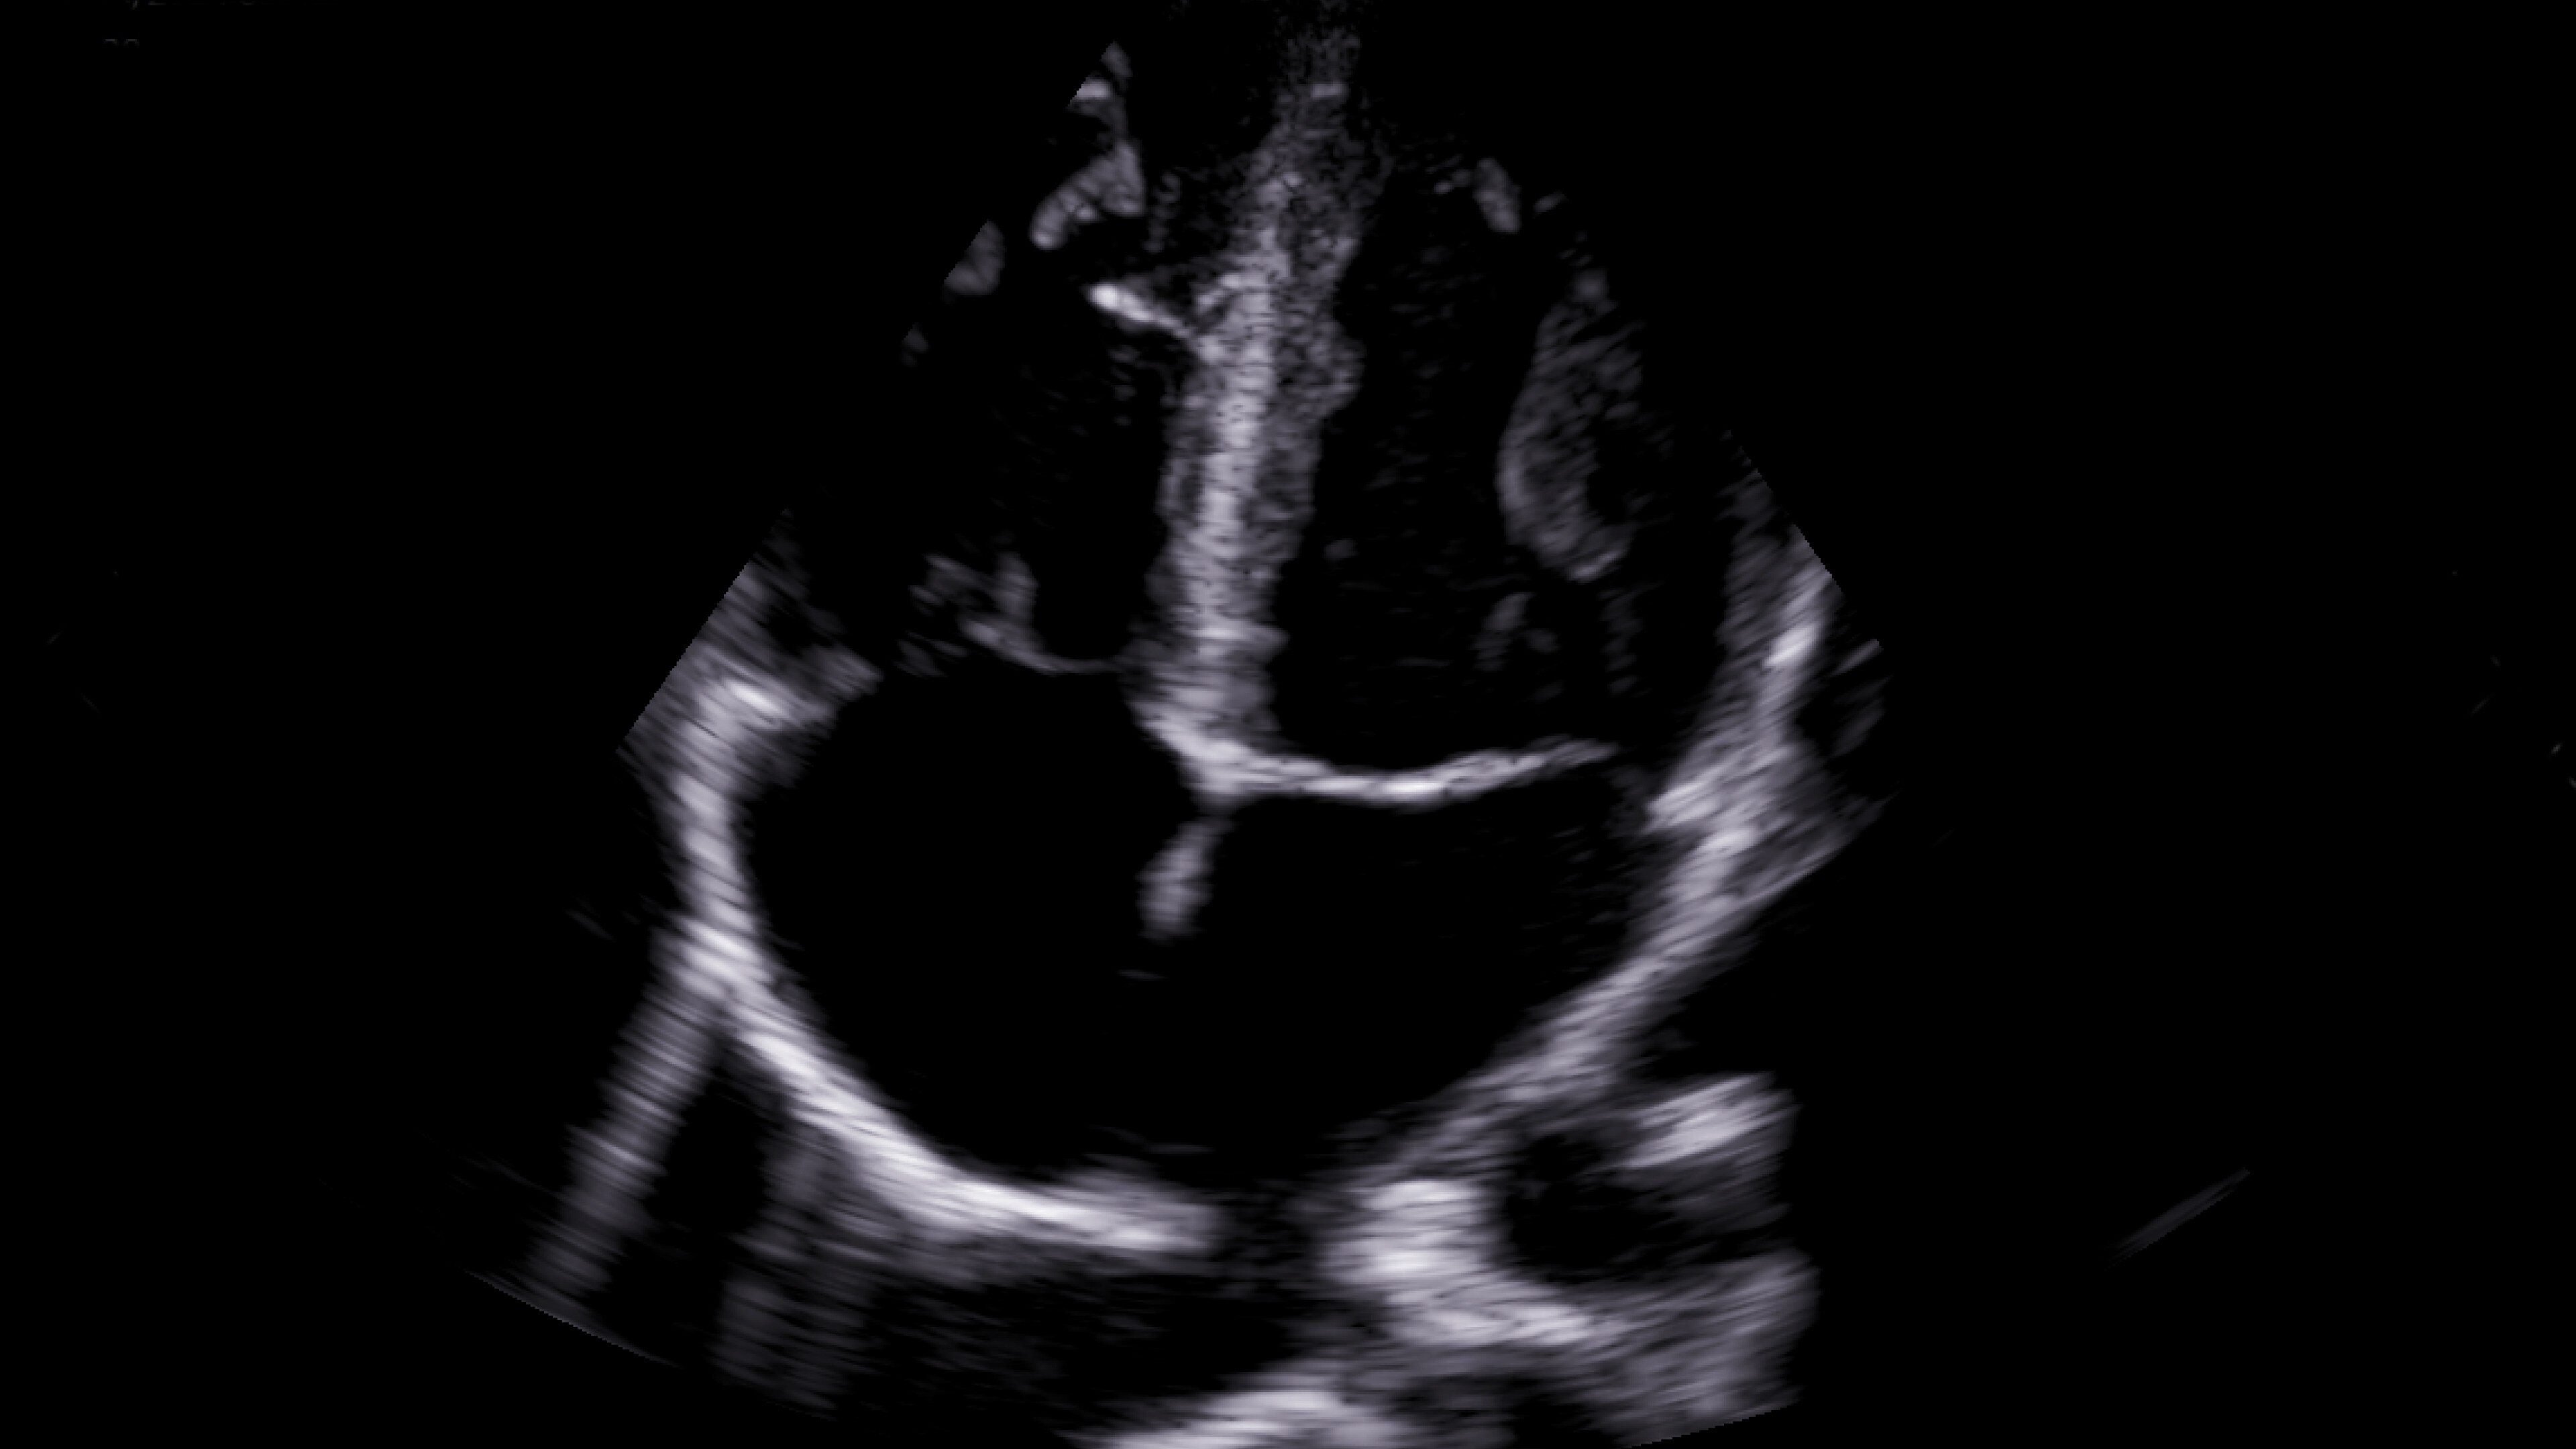

Small yet powerful

Flexible, wireless dual-probes deliver clear images and Venue family software